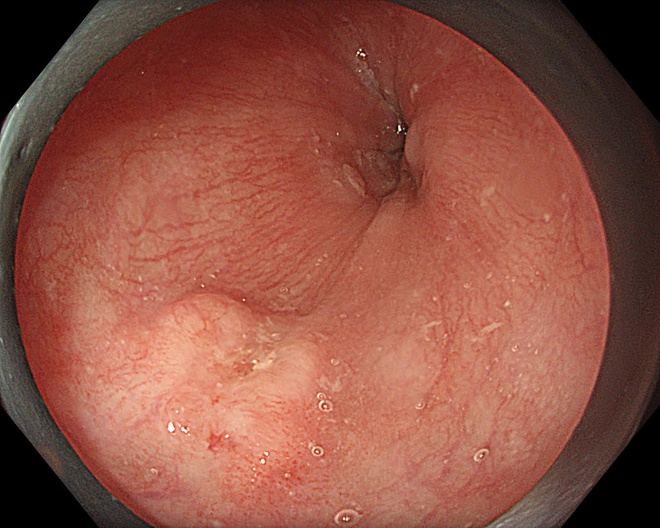

Một bệnh nhân 63 tuổi đã được phát hiện ung thư thực quản giai đoạn sớm nhờ công nghệ này và điều trị thành công, xuất viện sau 2 ngày.

Trong một trường hợp khác, bệnh nhân 67 tuổi được phát hiện tổn thương qua nội soi công nghệ cao. Tuy nhiên, qua đánh giá chuyên sâu, bác sĩ xác định tổn thương đã vượt chỉ định điều trị nội soi và chuyển sang phẫu thuật.

Kết quả mô bệnh học sau đó xác nhận ung thư đã xâm lấn dưới niêm mạc, phù hợp với chỉ định ngoại khoa.

Hình ảnh tổn thương thực quản của bệnh nhân.

Thực tế này cho thấy vai trò quan trọng của nội soi công nghệ cao kết hợp với kinh nghiệm lâm sàng trong việc đánh giá chính xác giai đoạn bệnh, từ đó đưa ra phương pháp điều trị phù hợp, tối ưu.